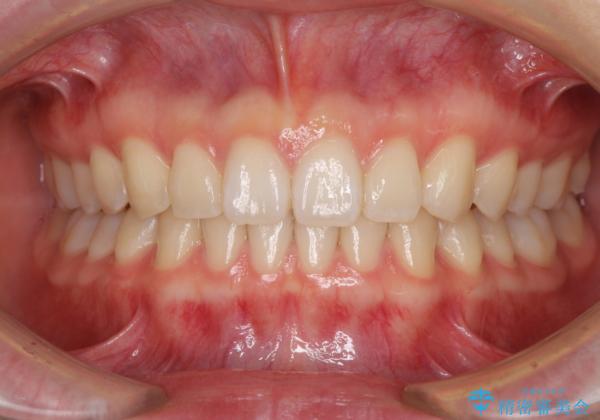

- 上の前歯の隙間を気にして来院された患者様です。

インビザラインにより、隙間を閉じながら、隙間の原因であるディープバイトを改善していくこととしました。